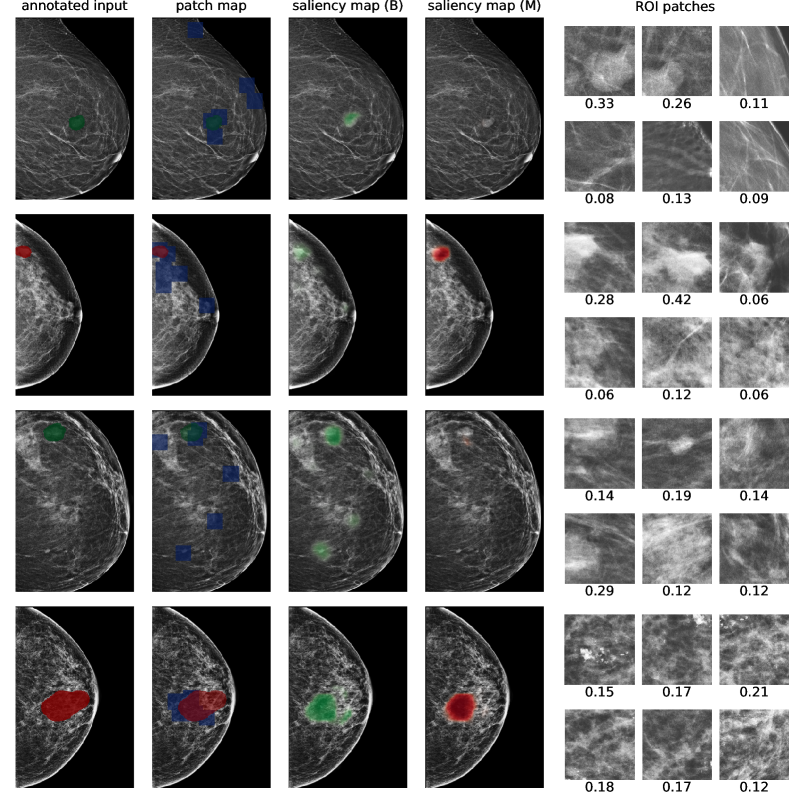

In Figure 7, we visualize saliency maps for four samples selected from the test set. In the first two examples, the saliency maps are highly activated on the annotated lesions, suggesting that our model is able to detect suspicious lesions without pixel-level supervision. Moreover, the attention is highly concentrated on ROI patches that overlap with the annotated lesions. In the third example, the saliency map for benign findings identifies three abnormalities. Although only the top abnormality was escalated for biopsy and hence annotated by radiologists, the radiologist’s report confirms that the two non-biopsied findings have a high probability of benignity and a low probability of malignancy. In the fourth example, we illustrate a case when there is some level of disagreement between our model and the annotation in the dataset. The malignancy saliency map only highlights part of a large malignant lesion with segmental coarse heterogeneous calcifications. This behavior is related to the design of : a fixed pooling threshold cannot be optimal for all sizes of ROI. The impact of is further studied in 3.6. This example also illustrates that while human experts are asked to annotate the entire lesion, CNNs tend to emphasize only the most informative regions. While no benign lesion is present, the benign saliency map still highlights regions similar to that in the malignancy saliency map, but with a lower probability than the malignancy saliency map. In fact, calcifications with this morphology and distribution can also result from benign pathophysiology [42].